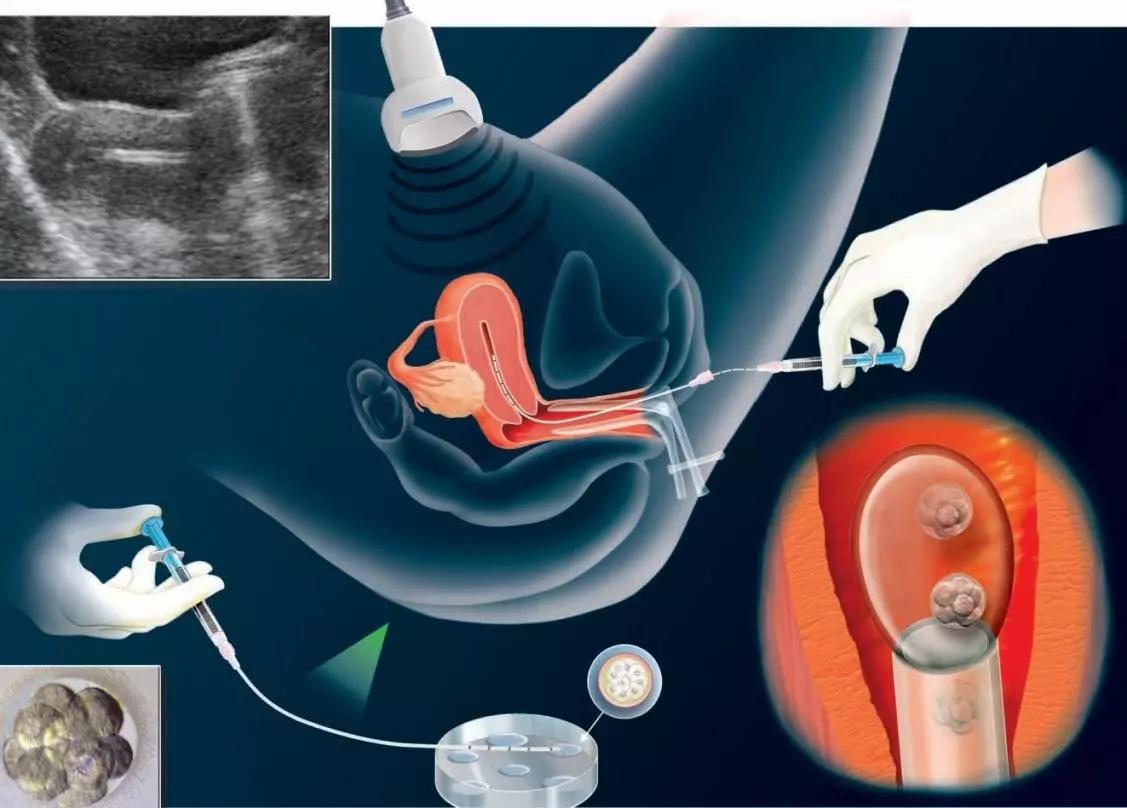

我们都知道体外受精胚胎移植技术(IVF-ET):又称试管婴儿,是指分别将卵子与精子取出后,置于试管内使其受精,再将胚胎移植回母体子宫内发育而诞生的婴儿。

一般在有或者无静脉麻醉下,经阴道B超引导,将取卵针穿过阴道穹窿,直达卵巢吸取卵子,并立刻在显微镜下将卵子移到含胚胎培养液的培养皿中,置37°C的培养箱中。

取卵后将处理后的精子与卵子放在同一个培养皿中,共同培养18小时后,可在显微镜下观察受精情况。若精子质量太差,无法自然受精,则需以显微注射法显微注射受精 即卵胞浆内单精子显微授精。